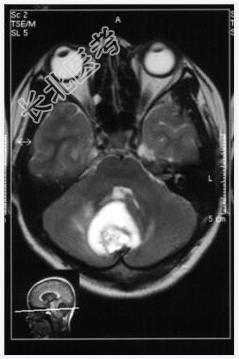

- [材料题] 患者,女性,19岁,因眩晕伴呕吐1周入院。体检:眼震,步态不稳,余未见异常。做头颅MRI检查。

- 简答题1、诊断及依据是什么?

- 简答题2、鉴别诊断有哪些?